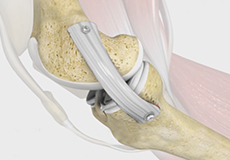

Knee Ligament Reconstruction